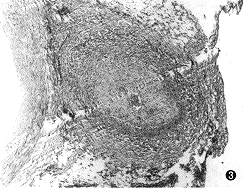

顱內占位性病變,常可通過影象學檢查獲得確診。影象學檢查包括頭顱CT掃描、核磁共振檢查及腦血管造影等。現代影象學檢查可顯示占位性病變的位置、大小、形態、數目,還能觀察到病變內部是否有囊變、壞死、鈣化、出血等。腦血管造影是根據血管的部位、形態的改變、循環時間的改變以及病理血管的出現等,間接了解病變的位置、大致形態、含血管是否豐富等。

4結果 採用此項技術,患者的頭痛、頭暈、嘔吐、失語、嘴斜、半身癱瘓等症狀在灌注藥物24-48小時後開始出現不同程度的減輕,部分半身癱瘓的患者恢復生活自理。2個月後對患者進行頭部CT檢查,發現患者顱內腫瘤均有不同程度的縮小,且術中出血少,腫瘤組織部分壞死.顱內惡性轉移瘤最長目前已存活16個月,平均6-10個月,同時提高了生存質量.患者在灌注化療藥物後基本無噁心嘔吐等胃腸反應,患者無寒戰、胸悶、心慌等過敏反應,也無頭痛嗜睡等症狀發生。